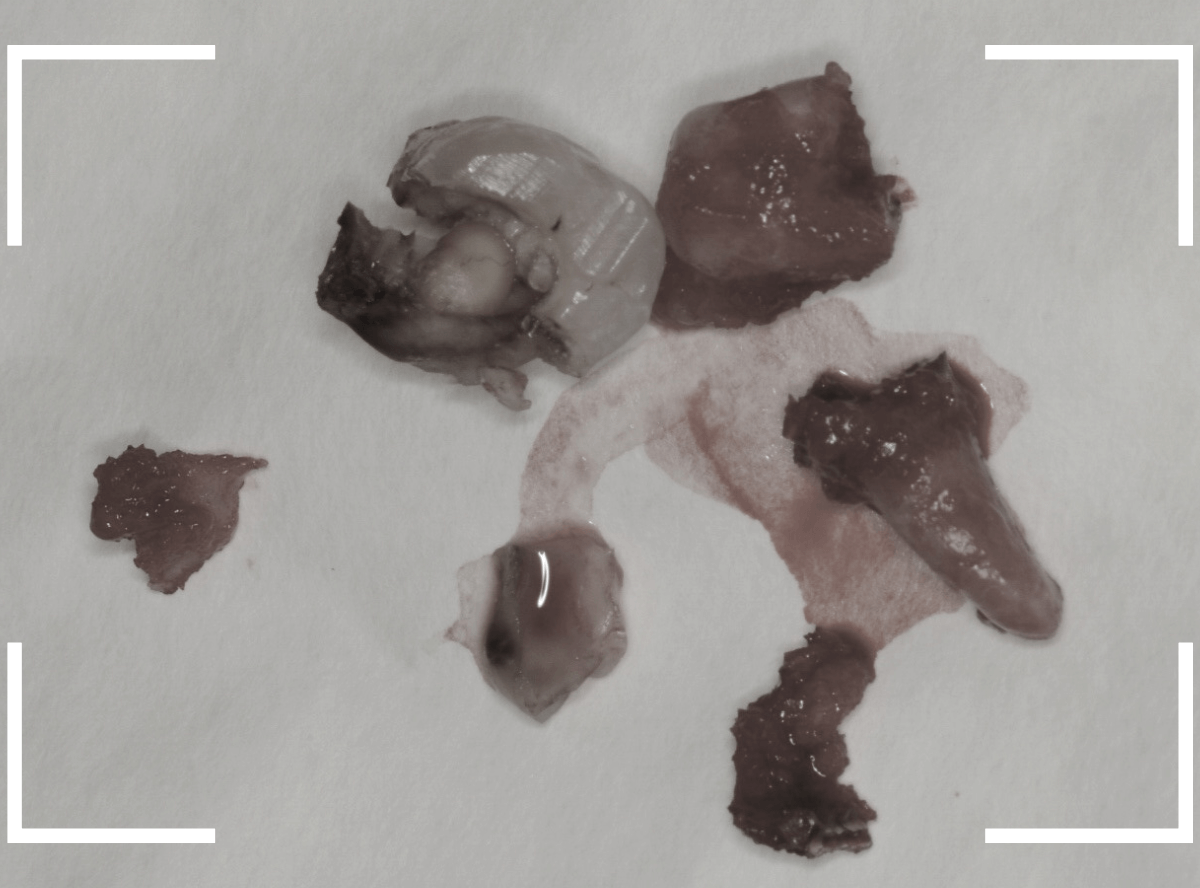

こちらが、抜歯後の写真です。

ここまで虫歯が進行していると、虫歯の治療をしても、ほとんど歯は残っていなかったでしょう。

歯の頭が無くなってしまうと、抜歯も困難にな行ってしまいます。

少しでも虫歯が進行しないうちに、と抜歯を行いましたが、やはりかなり手こずりました。

こちらが抜歯後のおやしらずの写真です。

根だけの状態になっていました(残根といいます)が、こちらは苦労なく抜歯できました。